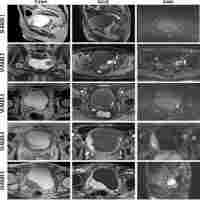

| Abstract | Background Vesical Imaging-Reporting and Data System (VI-RADS) based on multiparametric magnetic resonance imaging (mp-MRI) performed well in diagnosing muscle-invasive bladder cancer (MIBC). However, certain cases may present challenges in determining the final VI-RADS score using only T2-weighted imaging (T2WI) and diffusion-weighted imaging (DWI) sequences, especially in the absence of dynamic contrast-enhanced (DCE) imaging. This study aims to evaluates whether biparametric MRI (bp-MRI) achieve comparable diagnostic performance to mp-MRI for predicting MIBC and seeks to identify the most suitable bp-MRI criterion by establishing four specific conditions based on T2WI and DWI. Methods A retrospective analysis was conducted on 447 patients who underwent preoperative mp-MRI. Images were evaluated according to the VI-RADS protocol by three independent readers. In the bp-DWI and bp-DWI Plus criteria, DWI was the primary sequence used for lesion assessment, while T2WI was the primary sequence for bp-T2WI and bp-T2WI Plus criteria. The Plus criteria (bp-DWI Plus and bp-T2WI Plus) assigned a final VI-RADS score of 4 when both T2WI and DWI scores were 3. The gold standard for diagnosis was histopathological evaluation after surgery. Diagnostic performance was evaluated by comparing the area under the curve (AUC), sensitivity, specificity, and inter-reader agreement using Cohen’s kappa analysis. Results Among 447 patients, 304 confirmed as NMIBC and 143 as MIBC. The kappa values were 0.876, 0.873, 0.873, 0.642, and 0.642 for mp-MRI, bp-DWI, bp-DWI Plus, bp-T2WI, and bp-T2WI Plus, respectively, when VI-RADS cutoff > 2. Similarly, when cutoff > 3, the kappa values were 0.848, 0.811, 0.873, 0.811, and 0.873. No significant differences were observed between mp-MRI and bp-DWI (AUC: 0.916 vs. 0.912, p = 0.498), but mp-MRI and bp-DWI had higher AUCs compared to bp-DWI Plus, bp-T2WI, and bp-T2WI Plus. Conclusions Both mp-MRI and bp-DWI demonstrate excellent performance in predicting MIBC, with bp-DWI being an alternative to mp-MRI. Trial registration retrospectively. |